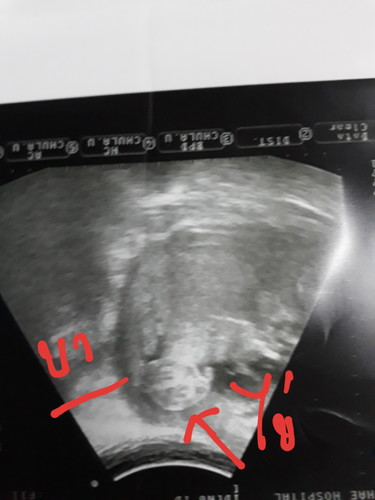

ผลซาวด์

สองเดือนก่อน หมอบอก 70% เพศ ญ มาเดือนนี้ หมอบอกเพศชาย น่าจะเป็นไข่ ไม่ใช่สายรกว่างั้น แม่ๆช่วยดูหน่อยค่ะ ไข่หรือรก?

น่าจะไข่นะคะแม่ ^^